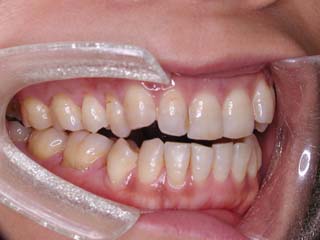

主訴:前歯の噛み合わせ

診断名:叢生を伴う開咬

年齢:28歳

使用した主な装置名:TPB、上顎リンガルブラケット矯正装置、下顎マルチブラケット装置、オーソアンカー SMAPシステム

抜歯/非抜歯および抜歯部位:非抜歯

治療期間:動的処置2年1か月、経過観察3年

本症例について検査診断の結果、開咬、叢生、下顎前突傾向を認めました。患者希望を考慮し、治療メカニクスとして、非抜歯配列、上顎のみリンガルブラケット矯正装置、下顎唇側マルチブラケット矯正装置、および、目的外使用のオーソアンカー SMAPシステムを用いることにいたしました。